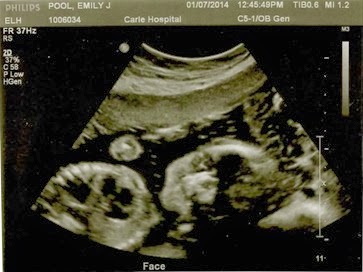

On Friday, December 20th, we loaded up the van with our bags packed for Peoria but took a detour to our 18/19 week appointment first with both kids in tow. The ultrasound felt a little long, but I chalked it up to trying to wrangle two kids while in that small room. Owen was pretty into it!

Several days after I found out I was pregnant, William had a very vivid dream that we had a baby who had down syndrome. He told me about it immediately but we hadn’t really talked about it since. Maybe it was simply a way of preparing us for this appointment and all the emotions that came with it. When Ellen finally came in, she informed us that our little man had choroid plexus cysts. It is one of the “soft markers” they use for downs and trisomy 18. She reassured us that the chances of there actually being something wrong were very very small. And we actually left the appointment with a lot of peace.

But less than a week later, my blood results came back great! While I know we could have handled what ever challenges this little man brought us, we are so so thankful that we are having a healthy baby! Now to compromise on a name.